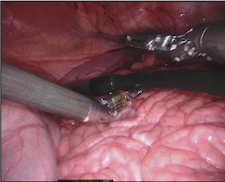

We provided the first 225 frames of 8 sequences as training data and kept the last 75 frames of those 8 sequences as test data. 2 of the full 300 frame sequences were kept as test sequences. Test labels were kept hidden from the participants. Our datasets contain 7 different robotic surgical instruments. The Large Needle Driver, Prograsp Forceps, Monopolar Curved Scissors, Cadiere Forceps, Bipolar Forceps, Vessel Sealer and additionally a drop-in ultrasound probe, which is typically held in the jaws of the Prograsp Forceps instrument. Samples from the training datasets are depicted in Fig. 2 and examples of the different instrument types are shown in Figure 3 and 4.